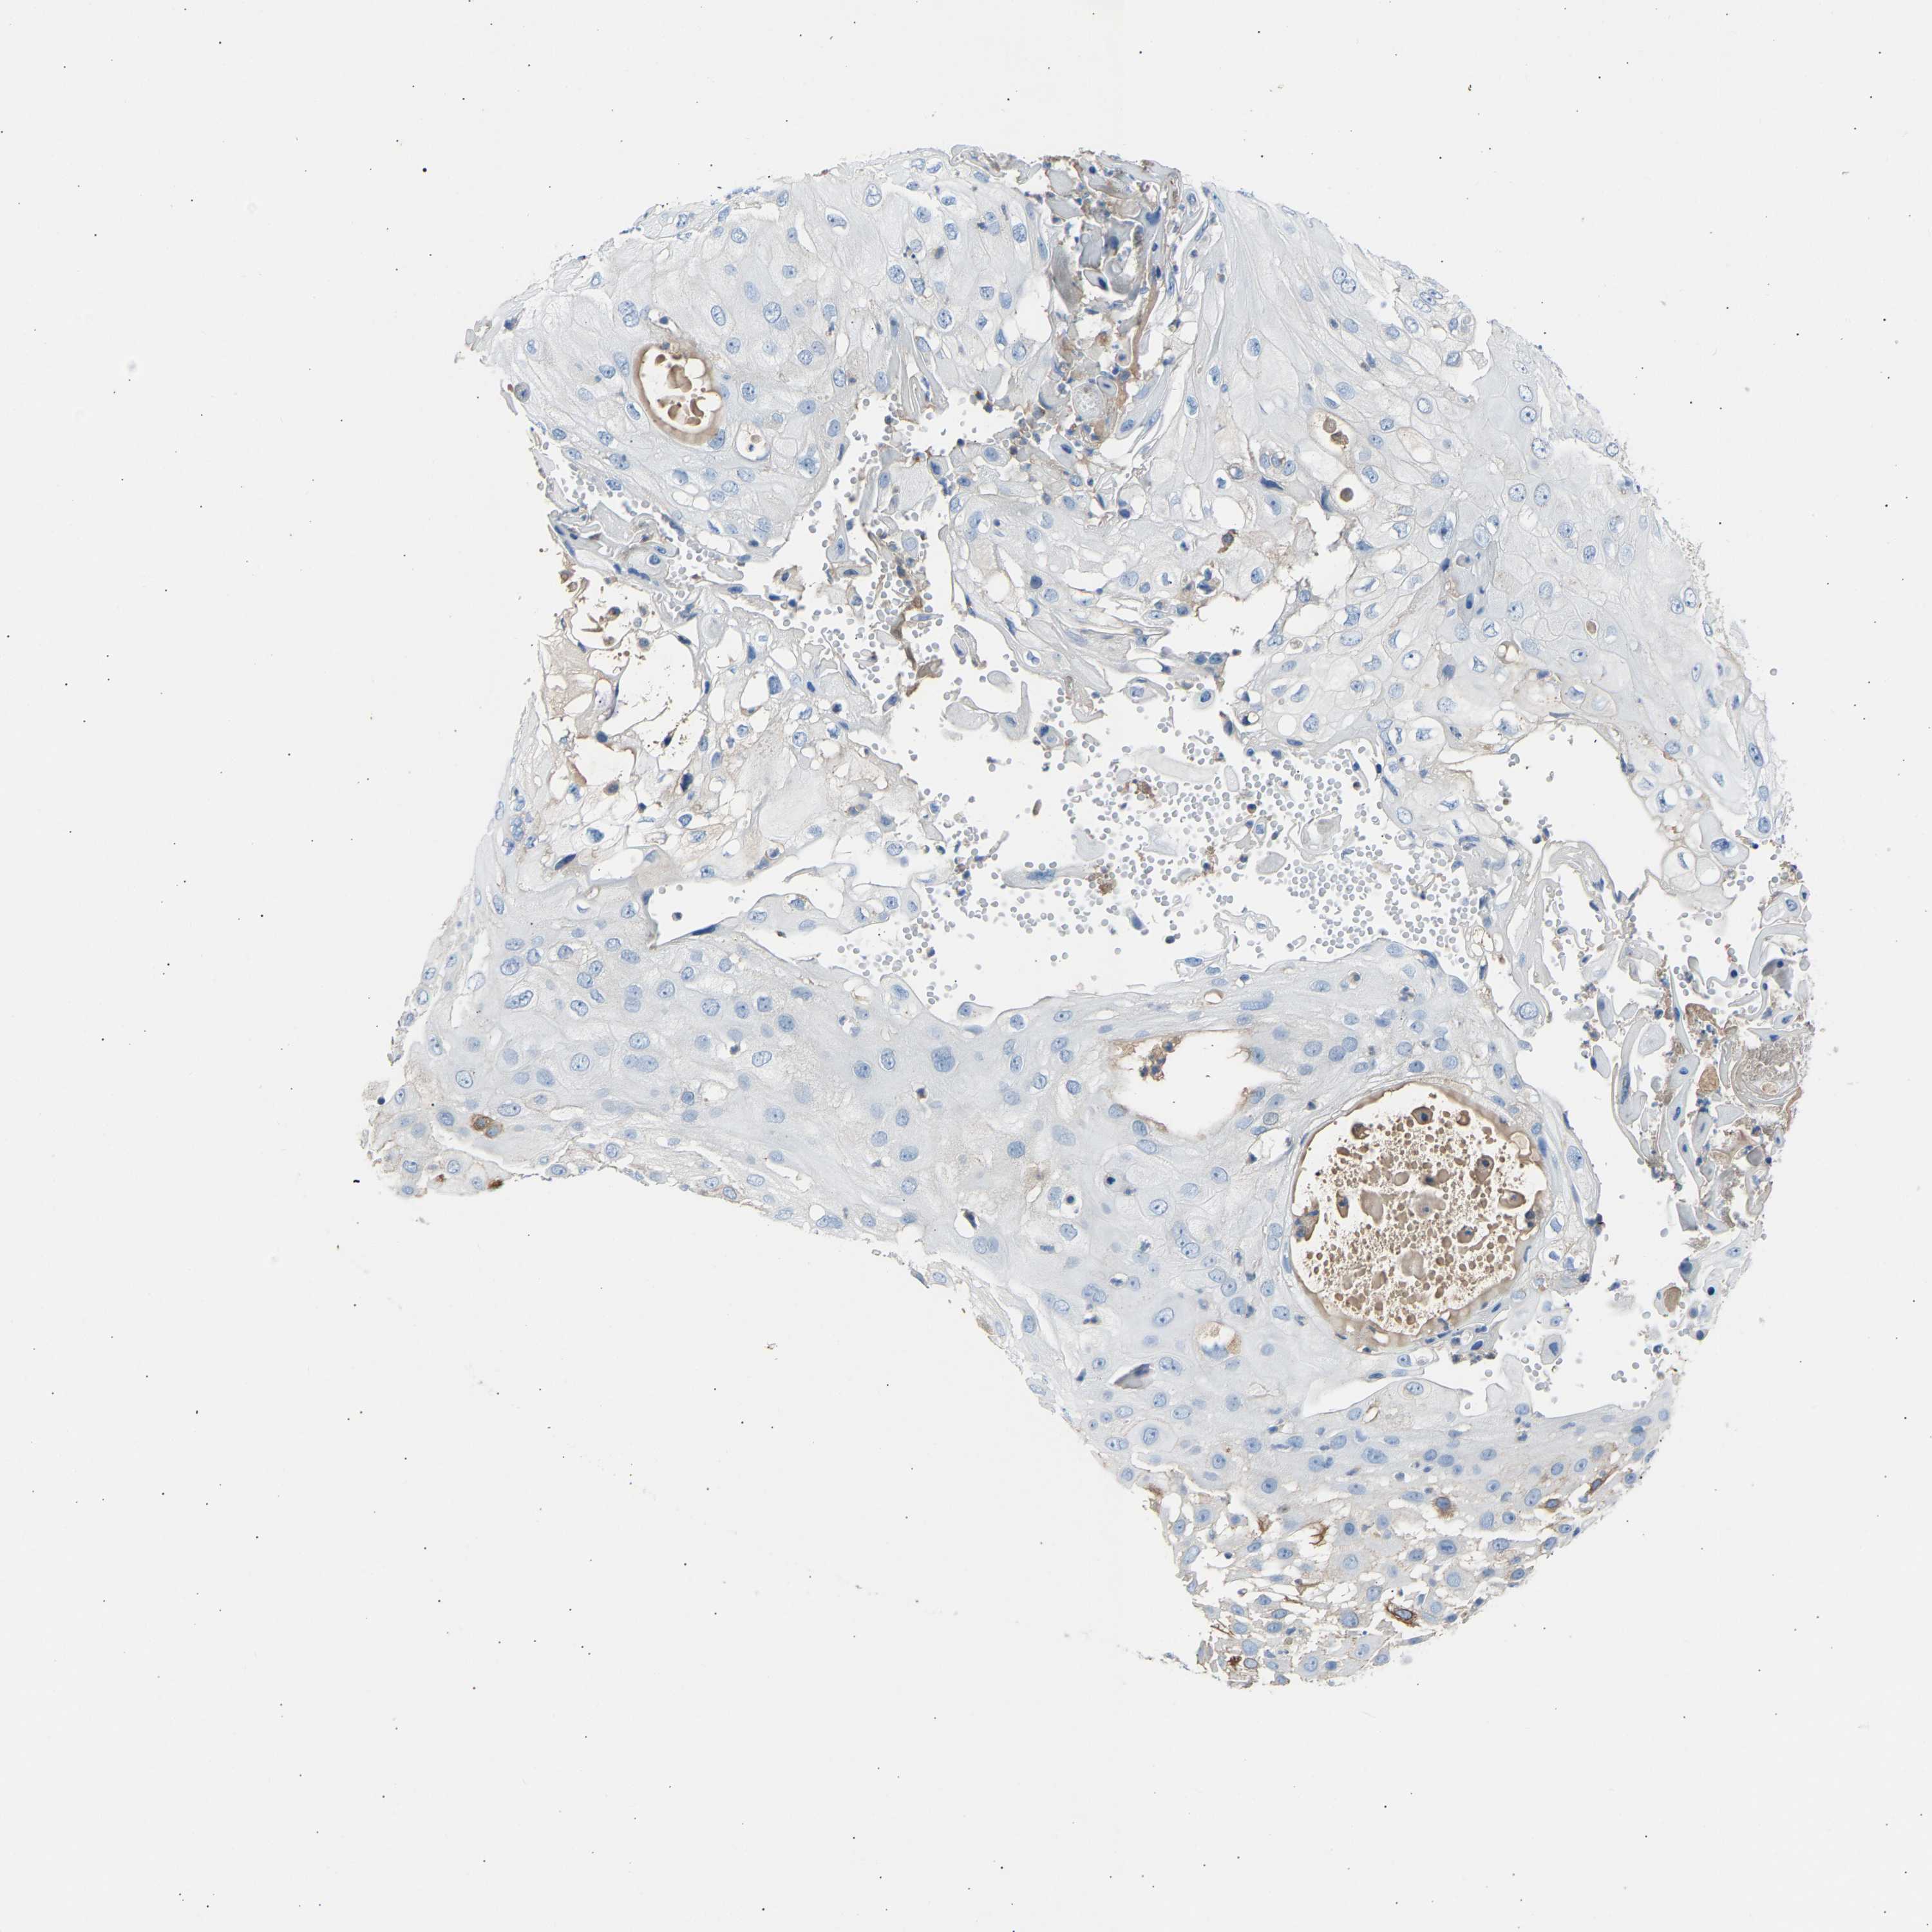

SKIN CANCER - Protein expressioni

A mouse-over function shows sample information and annotation data. Click on an image to view it in a full screen mode. Samples can be filtered based on level of antibody staining by selecting one or several of the following categories: high, medium, low and not detected. The assay and annotation is described here.

Each image is clickable and will lead to virtual microscopy that enables deeper exploration of all samples and also displays staining intensity scores, fraction scores and subcellular localization as well as patient and tissue information for each sample.

Antibody HPA020060

Squamous cell carcinoma, NOS